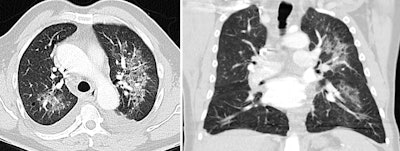

"Check for a typical pattern," the authors advised. "The presence of typical chest CT patterns can make the diagnosis straightforward, however they gain specificity when presenting in a characteristic clinical background. The main abnormalities, their distribution, and ancillary findings confirm the specific patterns."

Many of the conditions are not really urgent situations; they are subacute or progressive diseases. Patients often present at the emergency department for dyspnea, requiring a diagnostic approximation, and appropriately orienting those patients is desirable, they added.